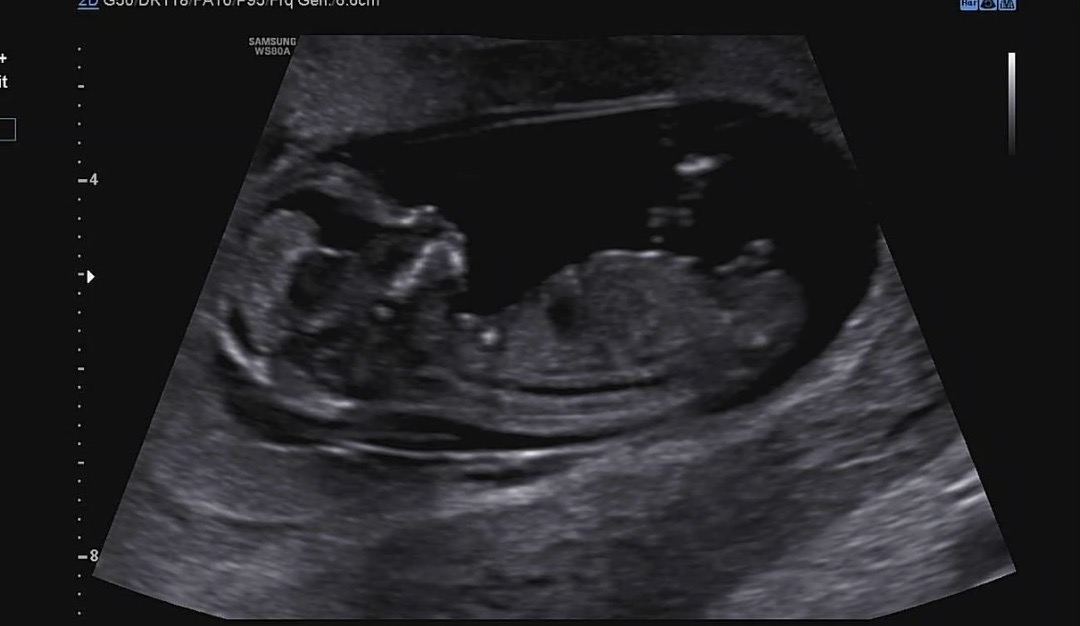

12주인데 각도법 봐주세요 딸인가요 아들인가요?

생식기 크기가 큰게 아들같아요